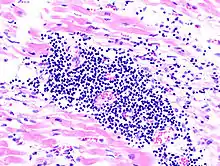

Virale Myokarditis

Ät.: Coxsackie-, ECHO-, Adenoviren, Influenzaviren

Pathogenese: Herzmuskelnekrose durch Virus und T-Zell-vermittelte Immunreaktion.

Mikro: Interstitielles lymphozytäres Infiltrat (kleine blaue Zellen), kaum Nekrosen.

![]() Virale Myokarditis bei Patient mit plötzlichem kongestiven Herzversagen, Autopsiepräparat, H&E. |